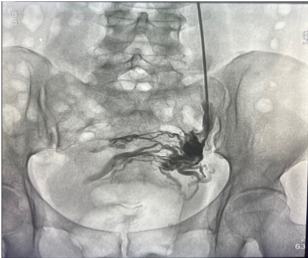

Patología venosa

Normalmente, las válvulas de las venas profundas de la pierna mantienen la sangre fluyendo de nuevo hacia el corazón. Cuando se presenta insuficiencia venosa por largo tiempo (crónica), las paredes de las venas se debilitan y las válvulas se dañan. Esto provoca que las venas permanezcan llenas de sangre, especialmente al estar de pie.